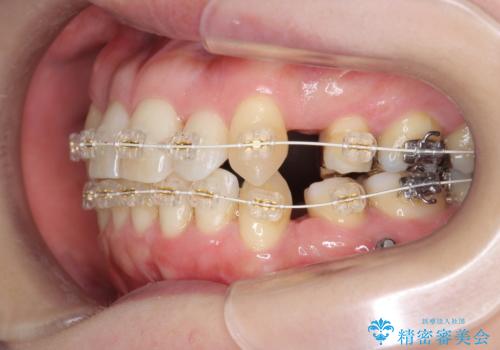

40代の矯正 八重歯を綺麗に

- 審美装置

- 2年3ヶ月

矯正用のミニスクリューを使用し、また、前歯をIPRすることで正中の左へのずれを最小限に抑えています。

上の前歯が内側に入っているクロスバイトは、笑った時に影になってしまい、かなり目立ちます。

内側に入っている前歯を外に出すだけで劇的に印象が変わります。